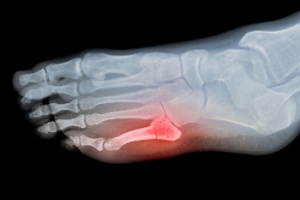

Most cases of gout are easily diagnosed by a podiatrist’s assessment of the various symptoms. Defined tests can also be performed. A blood test to detect elevated levels of uric acid is often used as well as an x-ray to diagnose visible and chronic gout.

A fracture of the 5th metatarsal, the long bone on the outside of the foot that connects to the little toe, can occur in several locations and patterns. One common type is an avulsion fracture, where a tendon or ligament pulls off a small piece of bone near the base of the metatarsal. Another type is a Jones fracture, which occurs slightly farther along the base, and is known for slower healing due to limited blood flow in that region. Additionally, a dancer’s fracture is an oblique break through the shaft of the bone, often caused by twisting or an awkward landing. These 5th metatarsal injuries typically result in pain, swelling, bruising, and difficulty walking. Proper diagnosis with imaging is important to distinguish between the types, as each can require a different treatment approach. A podiatrist can evaluate the extent of the injury and recommend immobilization or surgery, when necessary. If you believe you may have fractured a bone in your foot, it is suggested that you schedule an appointment with a podiatrist for an exam and appropriate treatment solutions.

A broken foot is caused by one of the bones in the foot typically breaking when bended, crushed, or stretched beyond its natural capabilities. Usually the location of the fracture indicates how the break occurred, whether it was through an object, fall, or any other type of injury.